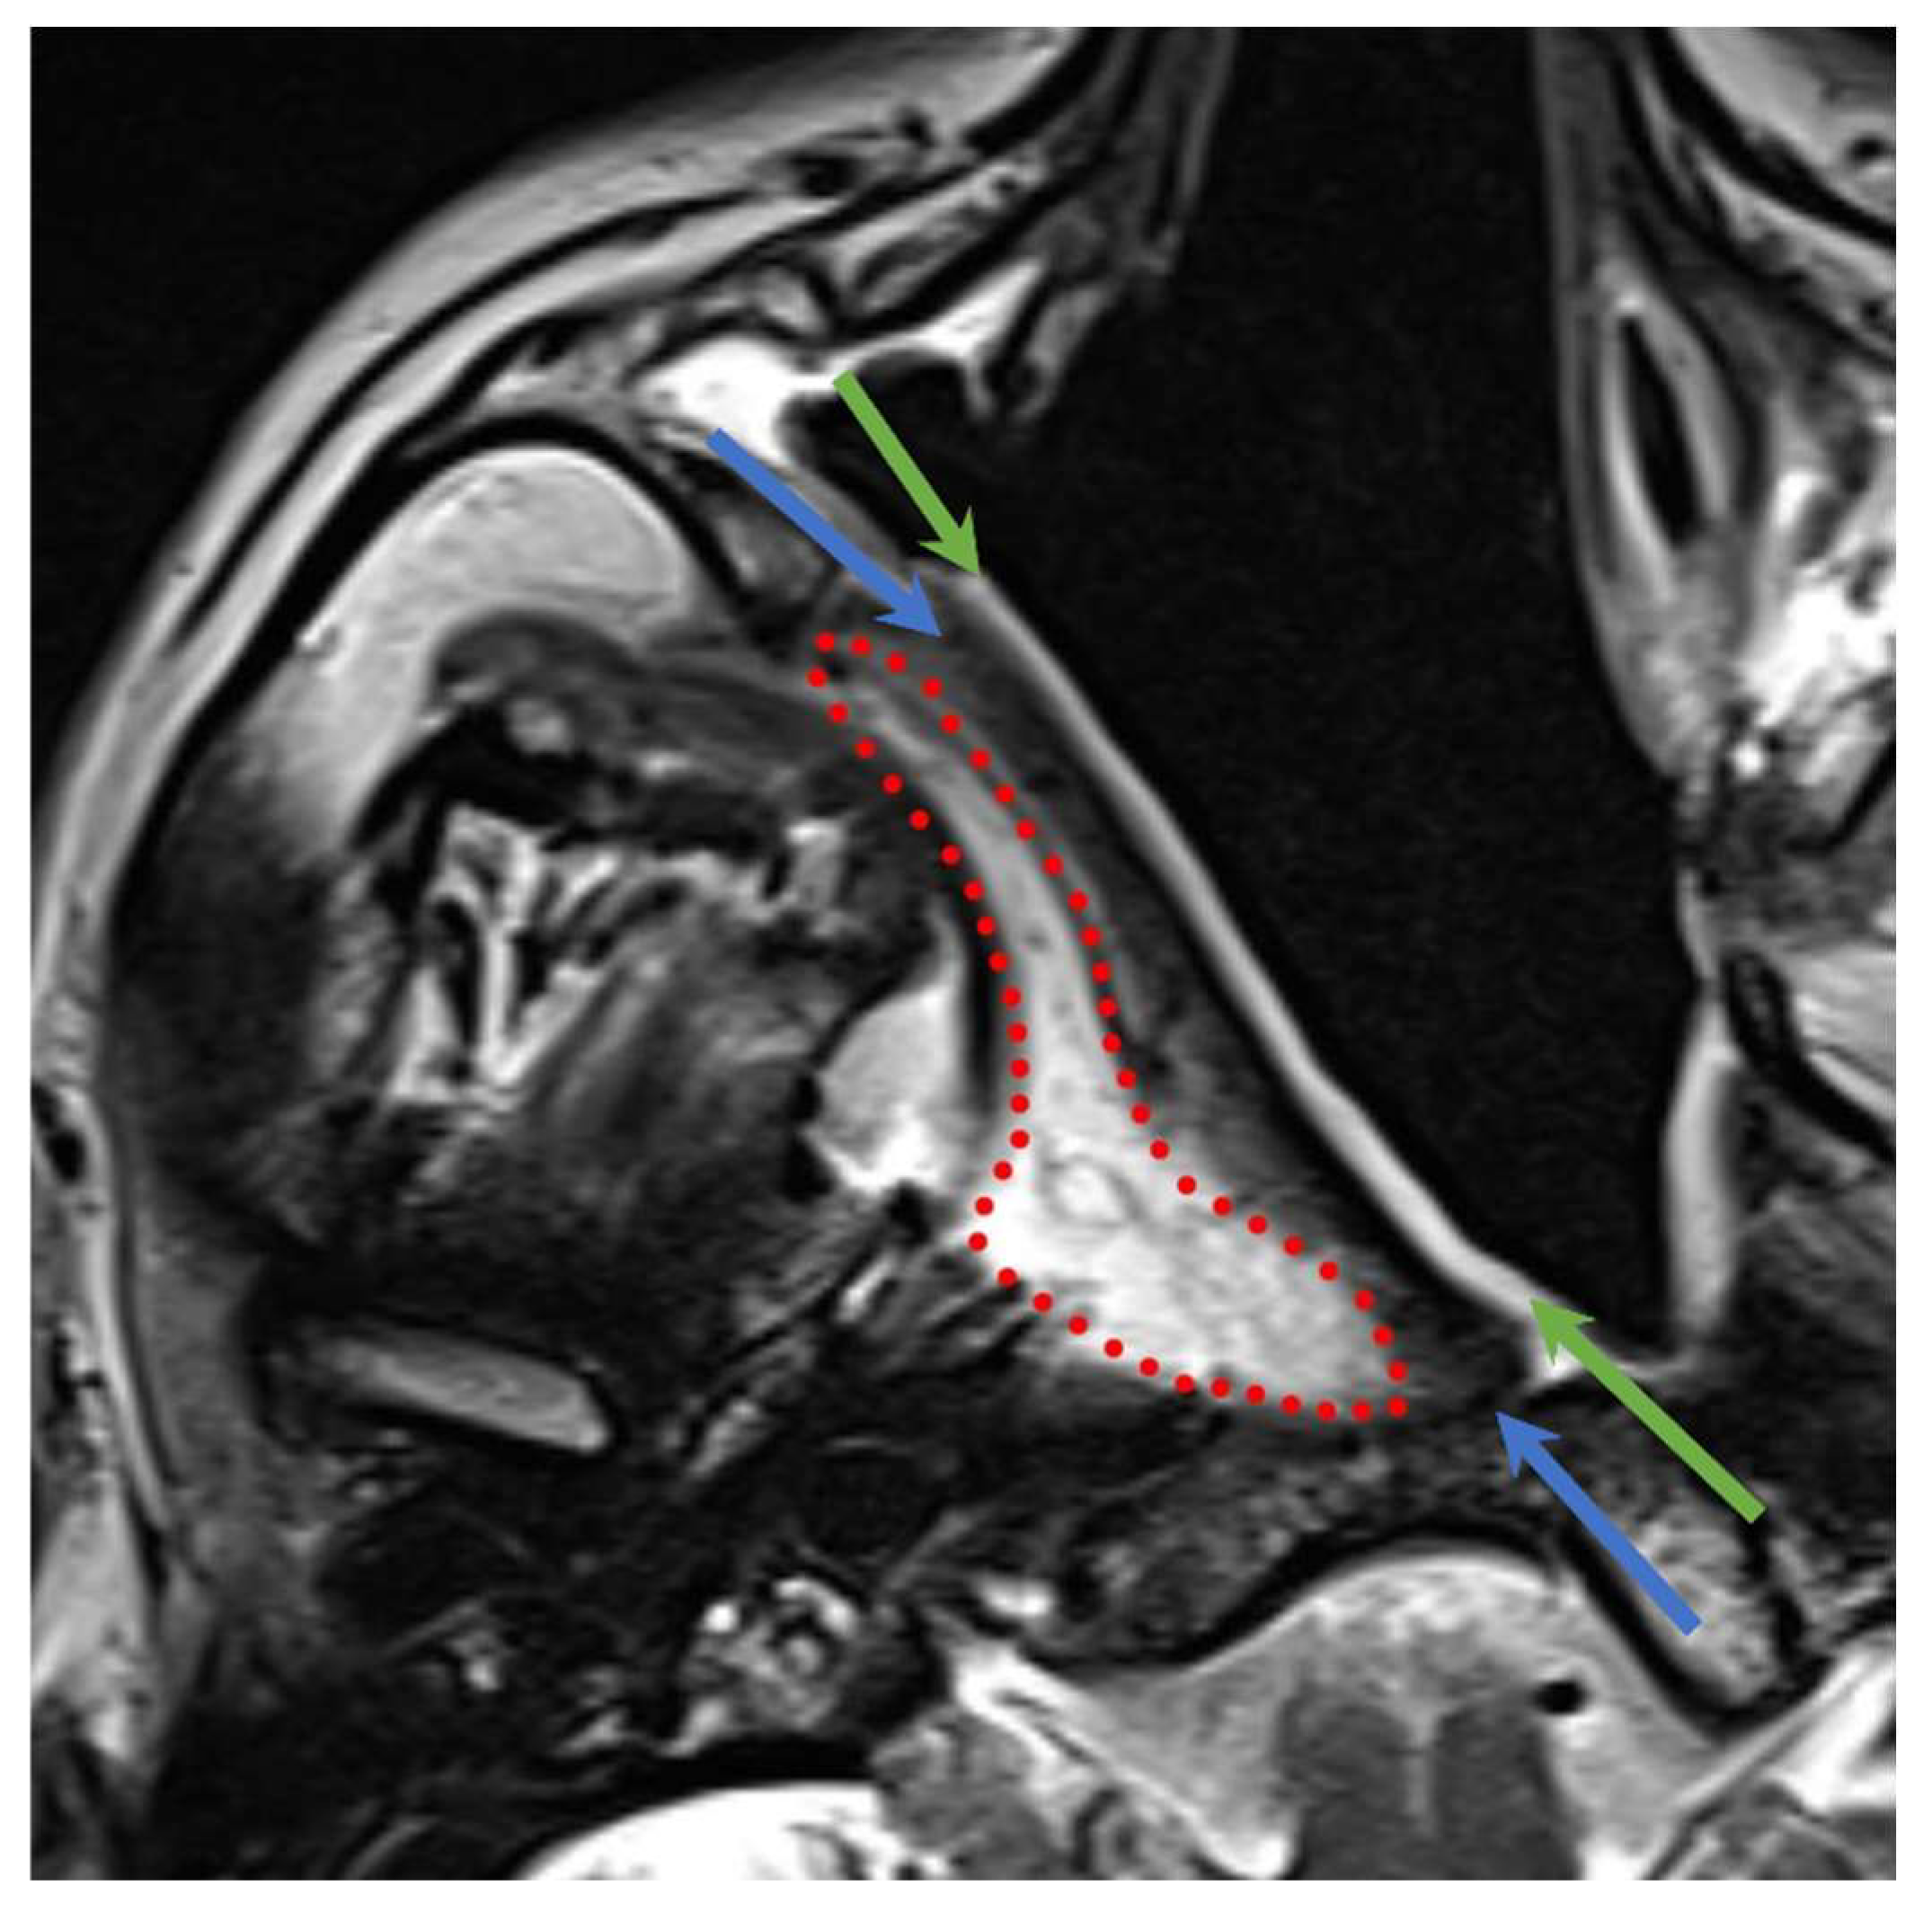

3.3.1. Nasoseptal Flap

- The mucosal layer showed a decrease in T2-signal intensity in more than half of the cases (four out of seven patients, 57%) and a reduction in enhancement in three cases (43%) at one year. In six out of seven patients (86%) the mucosal layer showed a thickness reduction one year after NER.

- The intermediate layer showed a decrease in the T2 signal in 86% of patients, while the T1 signal and enhancement were unchanged in the majority of patients (71%).

- The deep layer showed a T1 signal increase in five out of seven patients (71%), as shown in Figure 5.